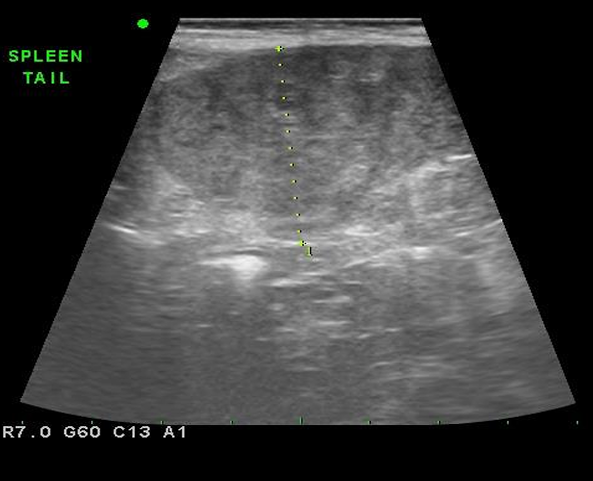

- Ultrasonographic evalation

- Variable size / Fine texture / Hyperechoic

☑️ 체표 림프절 종대 및 기력저하로 내원한 10년령 웰시코기에서 비장 초음파상 소견을 간략히 쓰고, 가장 가능성이 높은 진단명과 감별목록을 작성하시오.

- Splenomegaly, Honey-comb, swiss chesse appearance

- Dx) Splenic lymphoma (뚜렷한 저에코성의 honey-comb)